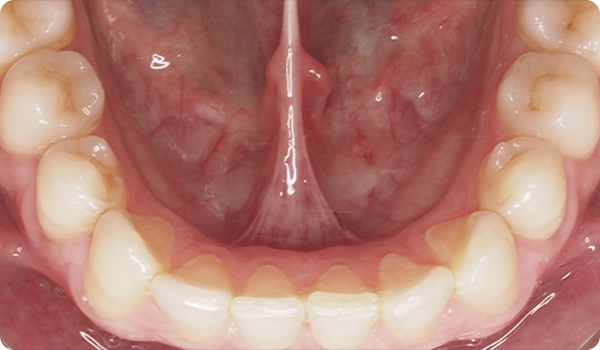

Designet til protetikere. Med små bevægelser korrigeres malpositioner og forbereder den mest egnede og konservative æstetiske behandling for dine patienter.

At justere tænder med Right er den perfekte og mest skånsomme forberedelse til fremtidig tandblegning eller facadebehandlinger, der vil perfektionere patientens smil.